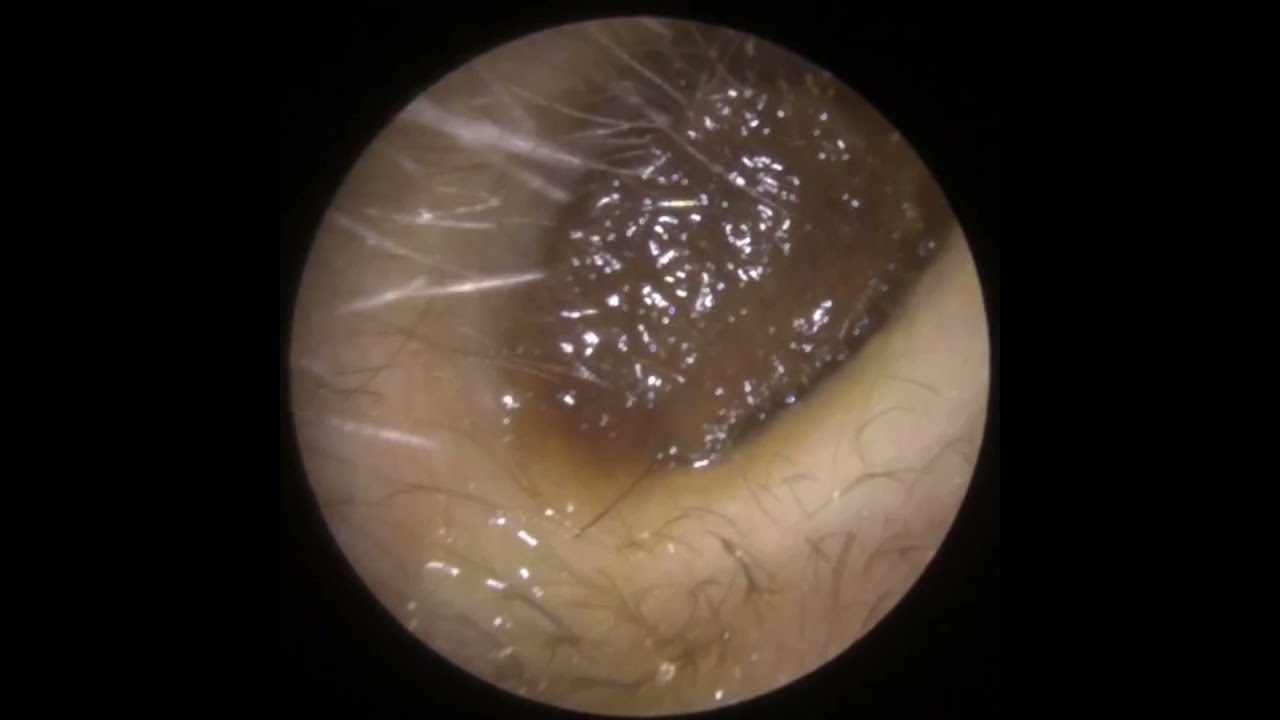

이주연은 사회적 고립, 노동 불안정, 기술 발전, 산업 독성학과 몸 정치학 등을 포괄한 광범위한 리서치와 인터뷰를 바탕으로, 분석적이면서도 시적인 논픽션 무빙 이미지를 연출한다.

Jooyeon Lee works with analytical yet poetic non-fiction moving image with expansive research and interviews to capture urban alienation, labour precarity, technological progress, industrial toxicology and body politics.